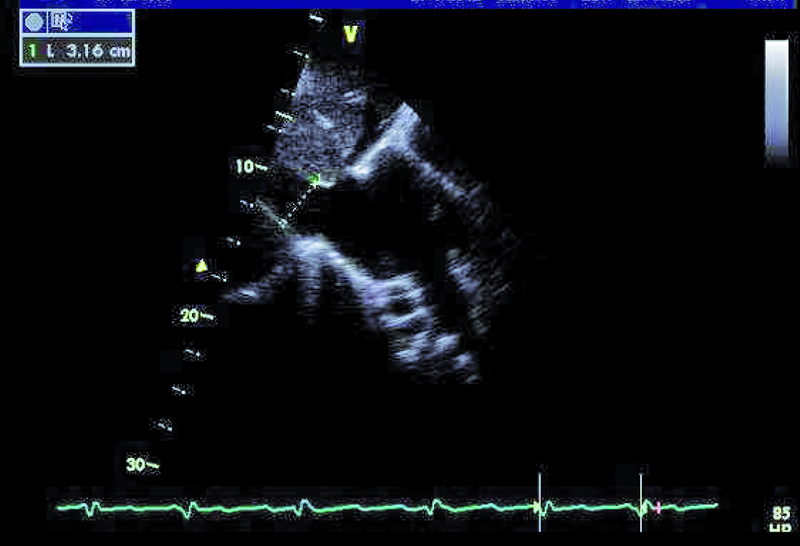

Szczegóły oceny układu krążenia z okresu przeprowadzanych operacji nie były znane. Można było jedynie przypuszczać, że śluzak prawej komory mógł zaburzać funkcję zastawki trójdzielnej, a jego resekcja pozostawiła stopniowo narastającą nieszczelność zastawki. Wymiana zastawki na biologiczną była konieczna, ale spowodowała dalsze problemy u chorego. Degeneracja zastawek biologicznych u osoby młodej może postępować dynamicznie, nawet bez obecności dodatkowych czynników nasilających to zjawisko, jak niewydolność nerek czy nadczynność przytarczyc. Kolejnym czynnikiem, poza wiekiem, wpływającym na odpowiedź immunologiczną, może być samo ujście trójdzielne, w którym procesy wapniowo-fosforanowe w odpowiedzi na rozciąganie płatków są silne. Warto także nadmienić, że zastawki biologiczne stentowe, jak użyta w tym wypadku, charakteryzują się szybszym tempem zwyrodnienia niż zastawki bezstentowe. Rozpoznanie strukturalnego zwyrodnienia bioprotezy w ujściu trójdzielnym nie powinno nastręczać trudności. Wczesnymi objawami procesu jest pogrubienie i usztywnienie płatków, które stają się w obrazie ultradźwiękowym jaśniejsze i nieregularne w zarysie (ryc. 1, 2). Ponieważ proces postępuje, włóknienie i zwapnienia obejmują najpierw spoidła, a następnie całe płatki i pierścień zastawki. W przedstawionym przypadku zwyrodnienie prowadzi zarówno do stenozy, jak i niedomykalności. O stenozie zastawki w ujściu trójdzielnym zawsze należy myśleć, gdy gradient średni napływu przekracza 6 mm Hg (ryc. 3). Niedomykalność trójdzielna uważana jest za istotną, kiedy talia strumienia ma szerokość co najmniej 6 mm (ryc. 4). Warto dodać, że rejestrowane zmiany hemodynamicznie są podobne do tych, jakie obserwuje się w natywnej zastawce trójdzielnej np. w rzadkim uszkodzeniu poreumatycznym. Chory ma wskazania do kolejnej interwencji kardiochirurgicznej i operacja w tym wypadku nie powinna być odkładana, żeby nie doprowadzić do narastającej niewydolności jam prawego serca. By uzupełnić ocenę, zarejestrowano projekcję na drogę odpływu prawej komory (ryc. 5). Wykluczono cechy nadciśnienia płucnego i niedomykalność zastawki płucnej. Zwrócono uwagę na istotnie poszerzone jamę prawego przedsionka i żyłę główną dolną (ryc. 6), odpowiadające nieprawidłowościom w badaniu fizykalnym – hepatomegalii i obrzękom obwodowym. Poza operacją można rozważyć wykonanie zabiegu techniką przezcewnikową i wszczepienie zastawki Edwards SAPIEN lub Melody (valve-in-valve). W tym wypadku na decyzji o leczeniu operacyjnym zaważyły jednak preferencja chorego i doświadczenie ośrodka.